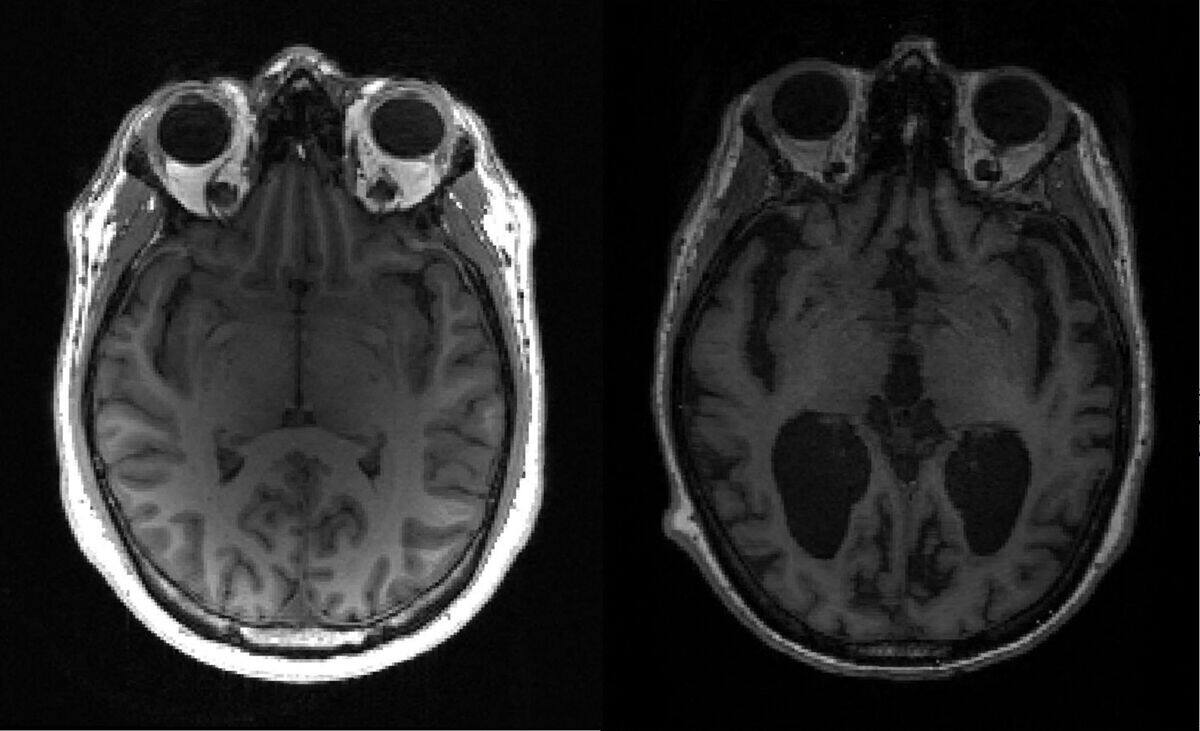

Des amas de protéines toxiques, qu’on pense responsables du déclin cognitif associé à la maladie d’Alzheimer, atteignent différentes zones du cerveau et s’y accumulent au fil des décennies, selon une nouvelle étude publiée vendredi.

Elle bouleverse également la théorie selon laquelle les amas se forment à un seul endroit et déclenchent une réaction en chaîne dans d’autres zones, un schéma constaté chez la souris. Une telle propagation peut se produire, mais n’est pas le moteur principal, selon les chercheurs.

Les chercheurs ont utilisé 400 échantillons de cerveau prélevés après la mort de personnes atteintes d’Alzheimer et 100 TEP-scan effectués sur des personnes qui vivent avec la maladie pour suivre l’agrégation de protéine tau.